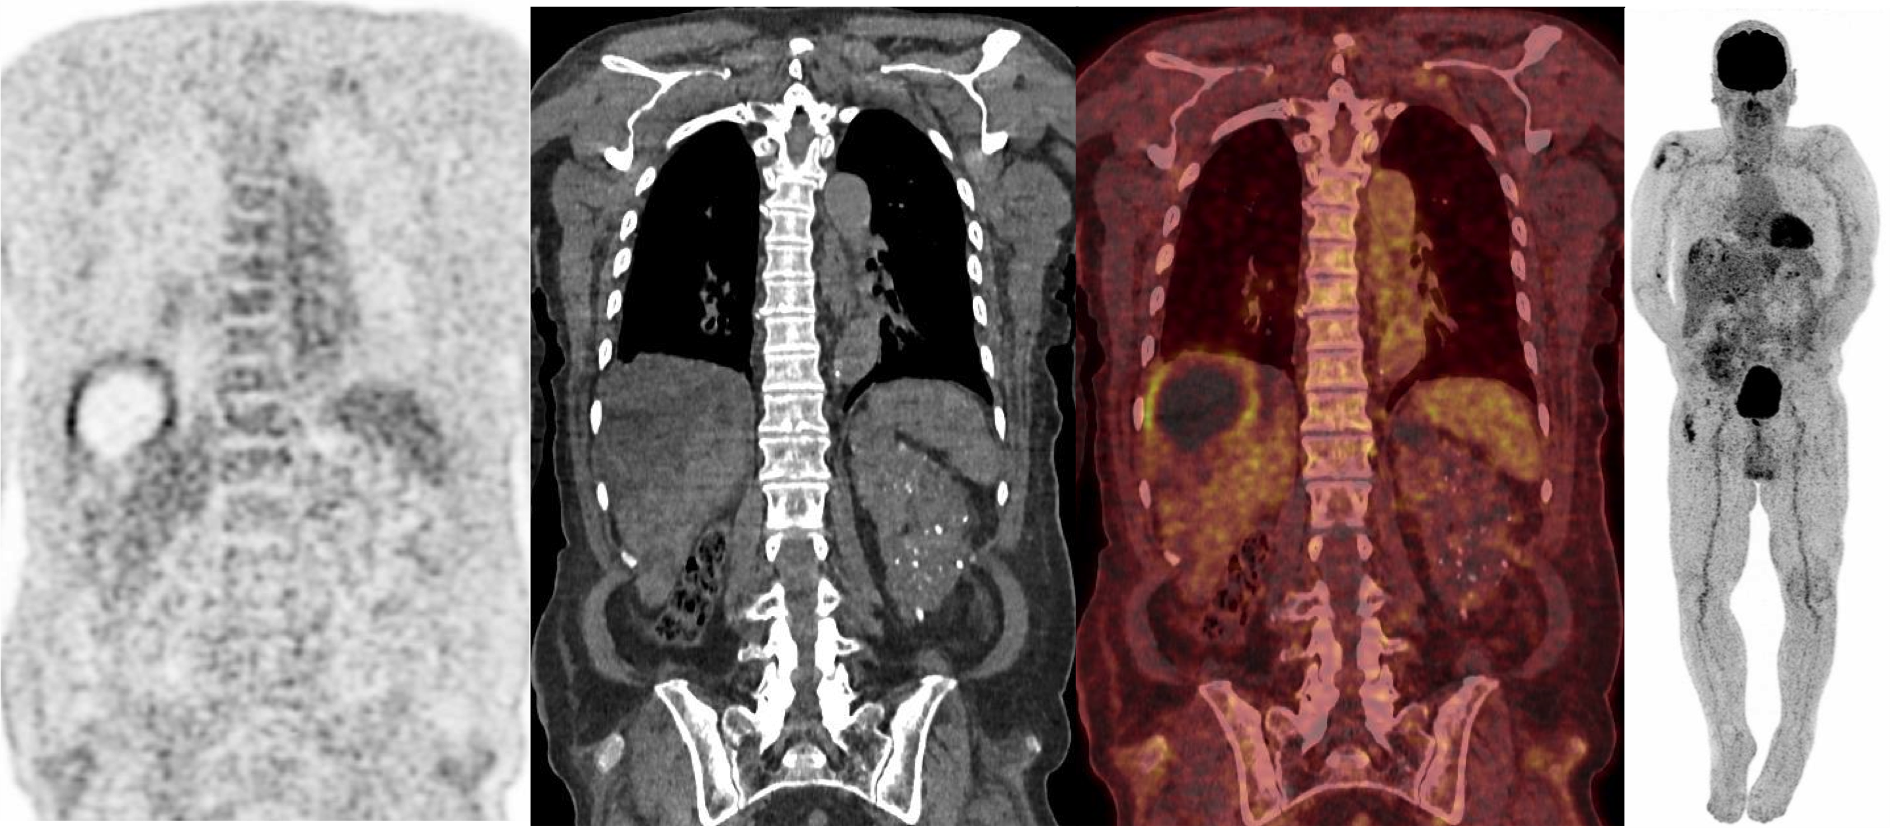

Il s’agit bien d’une infection de kyste hépatique sur polykystose hépato-rénale.

Sur les coupes axiales et coronales on ne voit pas d’activité au niveau rénal natif. Le greffon est visible en fosse iliaque droite sur le MIP.

Effectivement Chamia, l’image TEP peut faire penser à un kyste hydatique ; mais il n’y a pas de notion de voyage en zone endémique